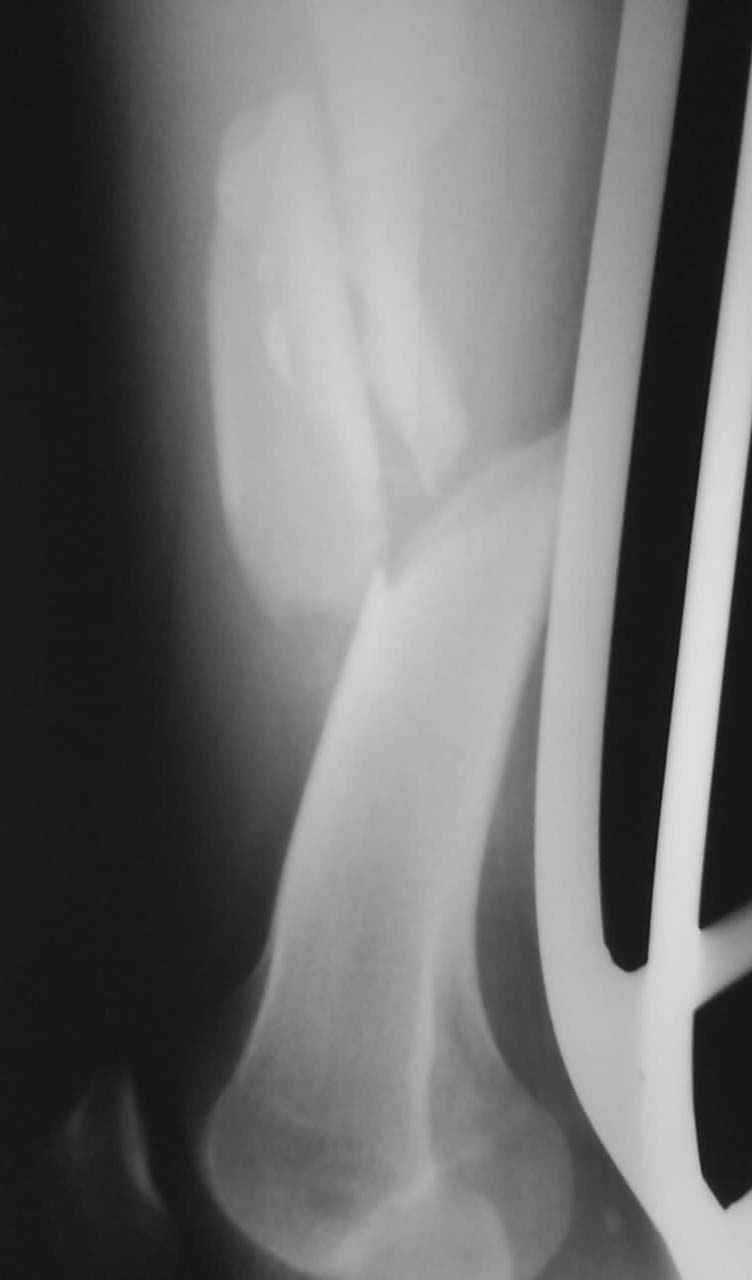

Привет из Нижнего Новгорода! К нам поступил пациент 25 лет с закрытыми переломами обеих бедренных костей, прошел месяц после травмы. Слева - внутрисуставной перелом, поэтому выбор здесь очевиден, открытая репозиция, стабильная фиксация, скорее всего LCP DF, а справа - мнения учёных, как говорится, разошлись. Лично я, как лечащий врач, за закрытый интрамедуллярный остеосинтез DFN. Со мной согласна половина коллектива, другая - за интрамедуллярный остеосинтез (DFN,UFN) но с открытой реопозицией, поскольку при закрытой методике все осколки останутся где-то сбоку, получится дефект и вдруг не срастется!Философский вопрос: что лучше - красивая рентгенограмма или сохранение кровоснабжения? Очень важно мнение коллег! Смирнов Алексей

Мы бы не стали открывать, такие переломы срастаются, хотя бы и с краевым дефектом. То есть если удалять стержень потом, то сильно попозже обычного. В приложении пример. Сразу после операции и через 11 мес. Понятное дело, пациент к тому времени давно и не хромал, и функция колена была полная.